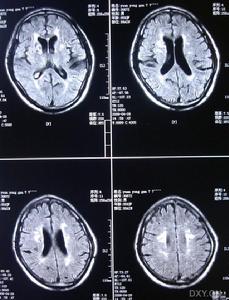

3.MRI是本病的重要診斷工具側腦室周圍及半卵圓中心可見均勻分布的點狀和結節狀T2WI高信號,基底核和腦橋也可見多數病人腦血管造影無異常,曾報告1例患者小動脈嚴重狹窄,另2例患者腦血管造影后神經體徵加重PET檢查僅1例嚴重基底核損傷的躁狂病人提示皮質代謝降低皮膚活檢是腦外部檢查的新手段,皮膚活檢發現嗜鋨顆粒樣物(GOM)沉積有重要診斷價值。可伴明顯抑鬱躁狂和自殺傾向,注意繼發的肺部感染尿路感染及褥瘡等。

影像學上有類似Binswanger病的表現,MRI顯示在腦室周圍白質、腦幹、小腦中腳、基底節區和丘腦部位多發性小的線狀、點狀病灶,可在皮質下對稱融合成片狀。CADASIL臨床確診標準:在可能CADASIL診斷標準的同時,與第19號常染色體連鎖和(或)病理證實有顆粒狀嗜鋨性物質沉積改變的小動脈病。可能為CADASIL的診斷標準:①50歲前發病;②出現下列臨床表現中至少2條:症狀持久的腦卒中發作、偏頭痛、明顯的情感異常、皮質下痴呆;③無腦血管病的危險因素;④常染色體顯性遺傳證據;⑤MRI顯示腦白質異常,而無腦皮質梗死灶。

⑥影像學檢查:MRI顯示非典型性腦白質病。可見,腦室周圍多發的梗死灶及白質變性,可累及兩側半球皮層、白質及腦室周圍、基底節、橋腦白質等部位。

影像學檢查示:患者姐弟的CT均可見,但當地的CT顯示欠清楚。患者的頭顱CT可見多發白質變性;MRI清晰可見多發白質變性及小梗死病灶,病灶大小不一,均呈長T1、長T2信號,病灶累及雙側半球、腦室周圍、腦幹、橋腦,小腦未見病灶;梗死灶分布在底節區,MRA(血管的磁共振影像)顯示顱內血管正常。